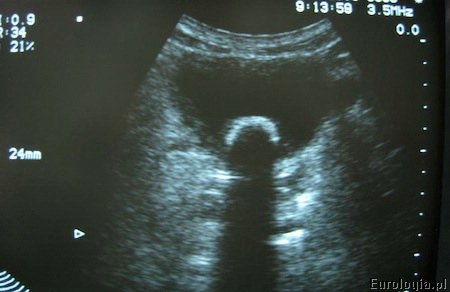

USG pęcherza moczowego

Badanie wykonywane jest w pozycji leżącej. Aby dokładnie ocenić pęcherz moczowy w USG konieczne jest jego dobre wypełnienie. Jeśli planujecie Państwo wizytę u lekarza z powodu podejrzenia kamicy pęcherza moczowego warto zabrać ze sobą butelkę wody i powstrzymywać się od oddania moczu bezpośrednio przed badaniem. Kamica pęcherza moczowego w większości przypadków jest dobrze widoczna w badaniu USG. Czasami - w przypadku złogów ukrytych za sterczem lub schowanych za spojeniem łonowym nie udaje się uwidocznić złogu w badaniu USG jamy brzusznej.

Fot. USG pęcherza moczowego - widoczne echo złogu